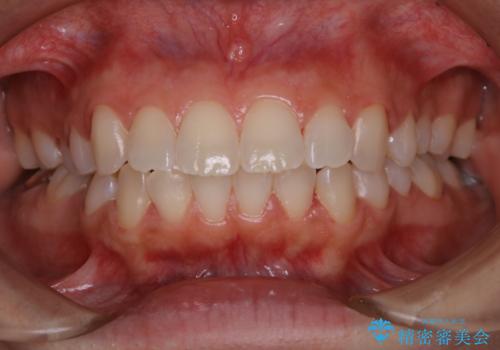

電子タバコによる着色をPMTCできれいに落とす